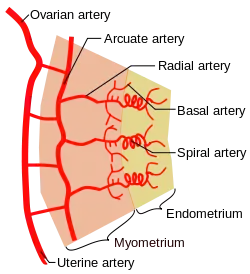

| Artery | Ovarian artery and uterine artery |

Blood supply

The uterus is supplied by arterial blood both from the uterine artery and the ovarian artery. Another anastomotic branch may also supply the uterus from anastomosis of these two arteries.